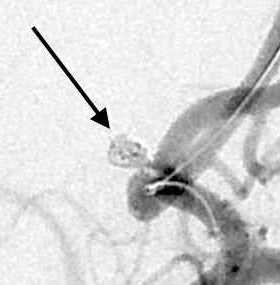

脳動脈瘤は脳にできた「血管のこぶ」であり、破裂すると「くも膜下出血」という生命を脅かす重大な病気にあることがあります。脳ドックなどで発見されて破れる前に手術をすることもあり、破裂しても再破裂を予防する目的で手術を行います。血管内治療では動脈瘤の中にコイルと呼ばれる柔らかい金属を詰めて固めることにより出血を予防することが可能で、開頭術と比べ遜色のない有効性と安全性が確立されています。その際にはステントや風船(バルーン)を使って正常の血管を塞栓しないように工夫をすることで安全性を高めています。